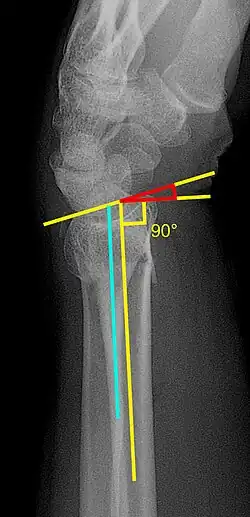

Various kinds of information can be obtained from X-rays of the wrist:[5]

Lateral view

- Volar or dorsal tilt - A line is drawn joining the most distal ends of the volar and dorsal side of the radius. Another line perpendicular to the longitudinal axis of the radius is drawn. The angle between the two lines is the angle of volar or dorsal tilt of the wrist. Measurement of volar or dorsal tilt should be made in true lateral view of the wrist because pronation of the forearm reduces the volar tilt and supination increases it. When dorsal tilt is more than 11 degrees, it is associated with loss of grip strength and loss of wrist flexion.[5]

Posteroanterior view

- Radial inclination - It is the angle between a line drawn from the radial styloid to the medial end of the articular surface of the radius and a line drawn perpendicular to the long axis of the radius. Loss of radial inclination is associated with loss of grip strength.[5]

- Radial length - It is the vertical distance in millimetres between a line tangential to the articular surface of the ulna and a tangential line drawn at the most distal point of radius (radial styloid). Shortening of radial length more than 4mm is associated with wrist pain.[5]

- Ulnar variance - It is the vertical distance between a horizontal line parallel to the articular surface of the radius and another horizontal line drawn parallel to the articular surface of the ulnar head. Positive ulnar variance (ulna appears longer than radius) disturbs the integrity of triangular fibrocartilage complex and is associated with loss of grip strength and wrist pain.[5]